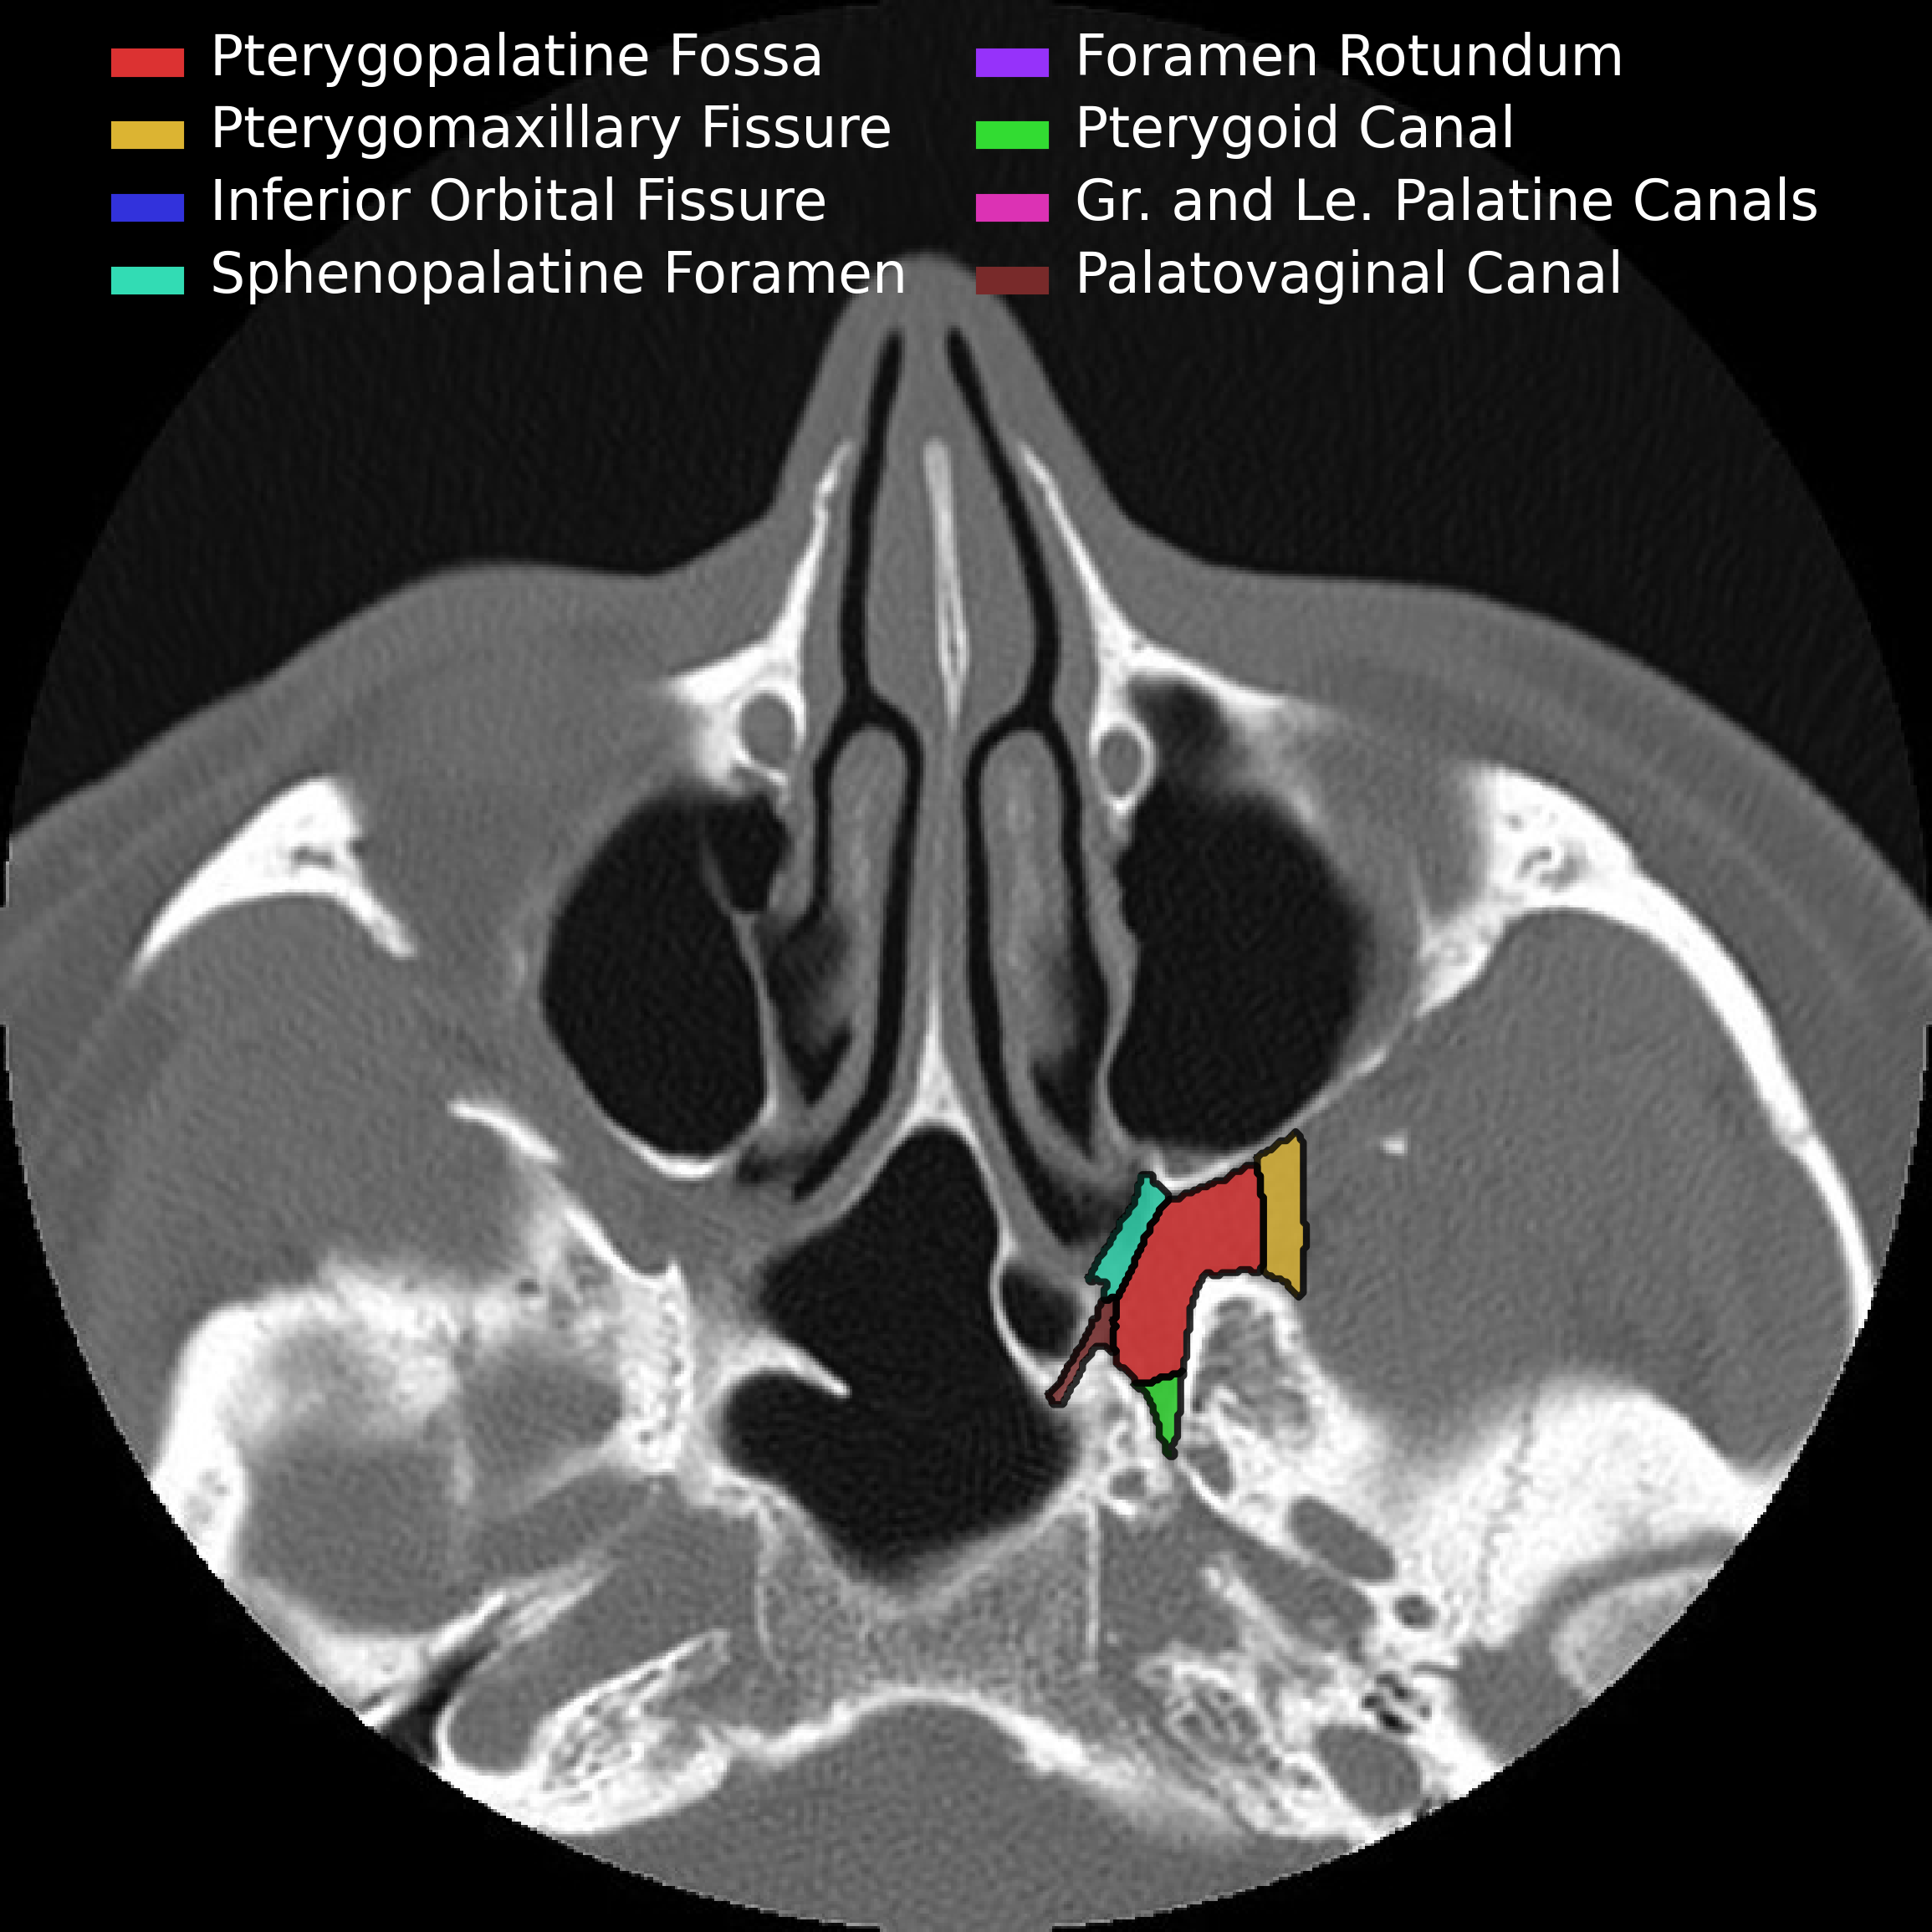

The following pictures are a fantastic way to visualize the borders rather than just memorizing them which is a sure fire way to forget them by tomorrow.

• Anterior & Superior - communicates with inferior orbital fissure

• Inferior - Greater & lesser palatine canals

• Communicates with palate

• Lateral - Pterygomaxillary fissure

• Communicates with masticator space

• Medial communication - Sphenopalatine foramen & Palatine bone

• Communicates with nasal cavity

• Transmits

• Sphenopalatine artery

• Posterior superior nasal nerves & nasopalatine nerve

• Posterior

• Posterior-medial - Palatovaginal canal

• Communicates with nasopharynx

• Transmits pharyngeal nerve and pharyngeal branch of maxillary artery

• Posterior-superior - Foramen rotundum

• communicates with Meckel cave & Cavernous sinus

• Posterior-inferior - pterygoid canal (aka vidian canal)

• Communicates with middle cranial fossa

• Transmits vidian nerve, artery and vein